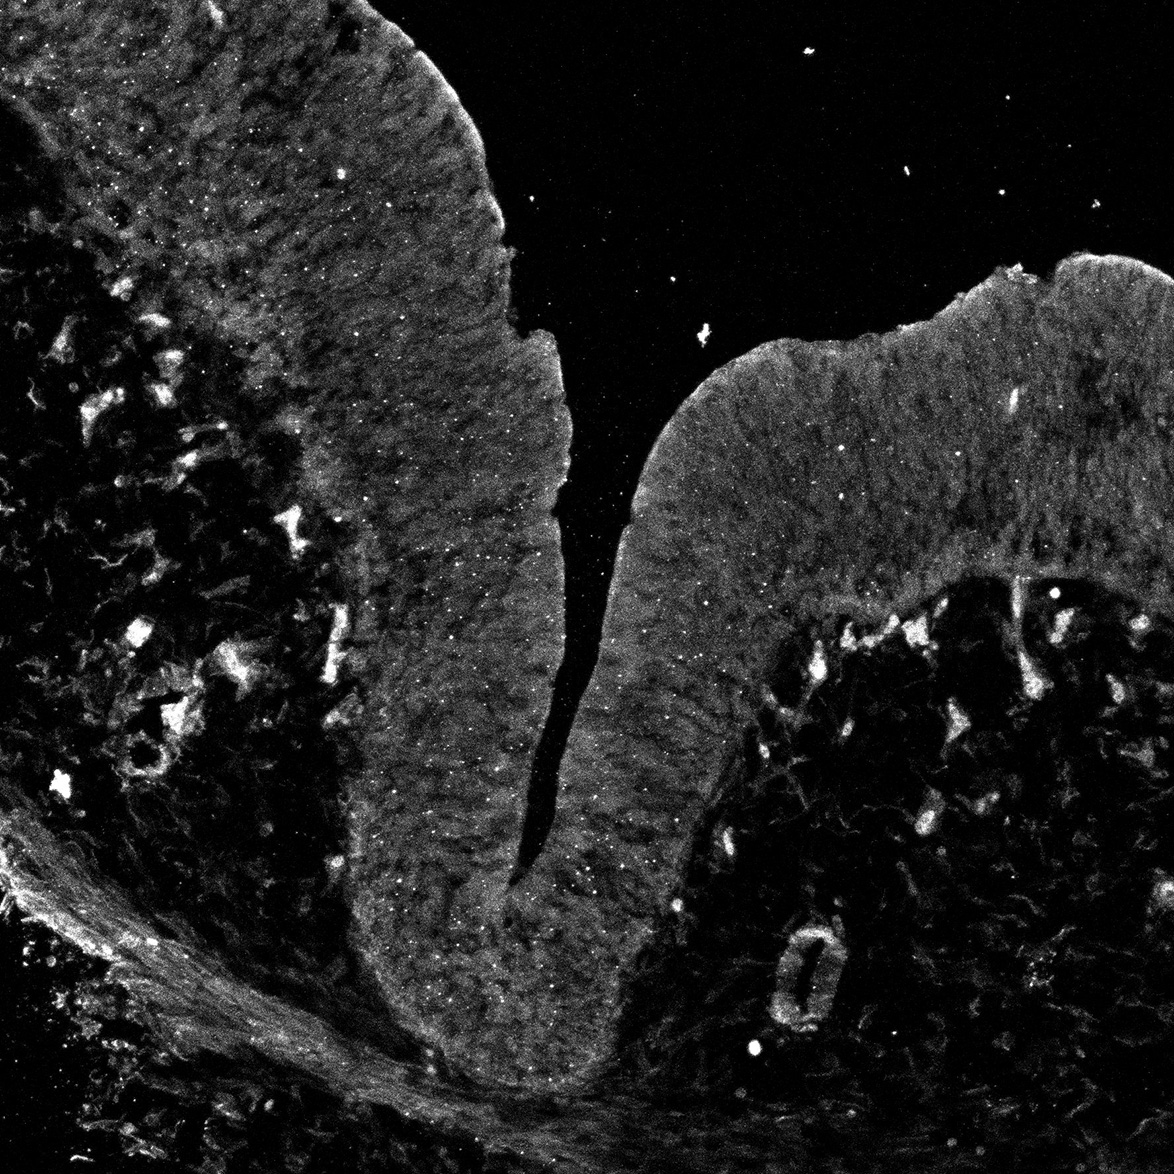

11PCW

DAPI

11PCW human midbrain

MAP2

SOX2

Merged